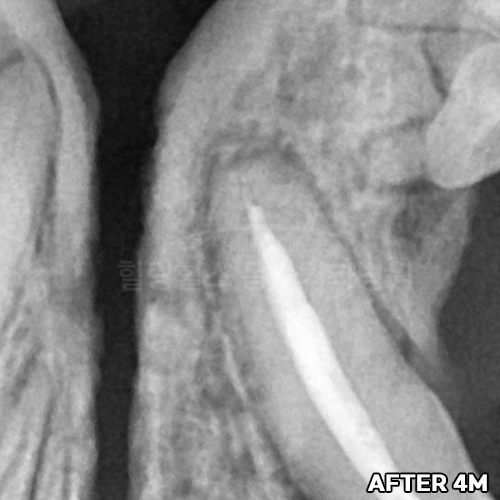

최고 난이도 강아지신경치료 - 꽉막힌 근관&치수괴사! 커다란 반려견치근단농양! 녹아내린 턱뼈! 치통으로 사나워진 모습! 강아지 신경치료 & 치주치료 한달 뒤 좋아졌어요!